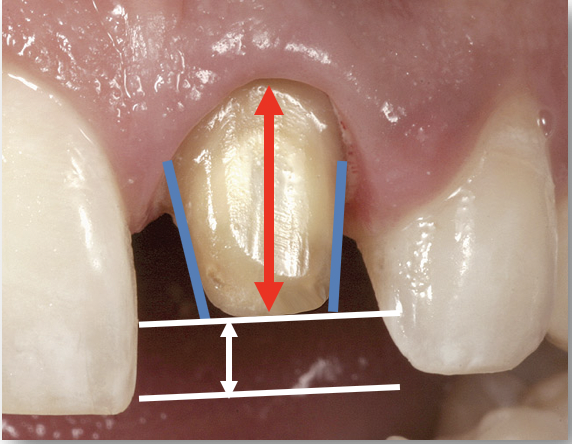

Fig 1. The most important factors to consider in preparing teeth for single-unit restorations are the taper, height, and reduction.

Figure 1

The most important factors to consider in preparing teeth for single-unit restorations are the taper (convergence), height (clinical crown height-how much tooth structure is above the gingiva and the height of the preparation), and reduction (Figure 1).6 Less than or equal to 20 degrees of taper or convergence is clinically appropriate. Overly tapered preparations will prevent the final restoration from being retentive. A preparation that is modestly parallel, while still achieving a good draw, is optimal. A 4-mm crown height is minimally adequate. If the height of the preparation is less than 4 mm, additional retentive features should be considered, such as slots and grooves in the preparation.